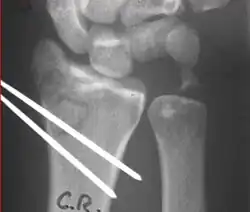

Closed reduction of a distal radius fracture involves first anesthetizing the affected area with a hematoma block, intravenous regional anesthesia (Bier's block), sedation or a general anesthesia.[5] Manipulation generally includes first placing the arm under traction and unlocking the fragments. The deformity is then reduced with appropriate closed manipulative (depending on the type of deformity) reduction, after which a splint or cast is placed and an X-ray is taken to ensure that the reduction was successful. The cast is usually maintained for about 6 weeks.[5]

Surgical options have been shown to be successful in patients with unstable extra-articular or minimal articular distal radius fractures. These options include percutaneous pinning, external fixation, and ORIF using plating. Patients with low functional demand of their wrists can be treated successfully with nonsurgical management; however, in more active and fit patients with fractures that are reducible by closed means, nonbridging external fixation is preferred, as it has less serious complications when compared to other surgical options.[5] The most common complication associated with nonbridging external fixation is pin tract infection, which can be managed with antibiotics and frequent dressing changes, and rarely results in reoperation.[5] The external fixator is placed for 5 to 6 weeks and can be removed in an outpatient setting.[5]

These fractures, although less common, often require surgery in active, healthy patients to address displacement of both the joint and the metaphysis. The two mainstays of treatment are bridging external fixation or ORIF. If reduction can be achieved by closed/percutaneous reduction, then open reduction can generally be avoided. Percutaneous pinning is preferred to plating due to similar clinical and radiological outcomes, as well as lower costs, when compared to plating, despite increased risk of superficial infections.[24] Level of joint restoration, as opposed to surgical technique, has been found to be a better indicator of functional outcomes.[5]